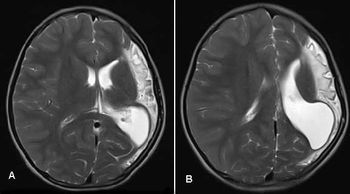

Dyke-Davidoff-Masson Syndrome Case 2 Dyke-Davidoff-Masson Syndrome Case 2- Published: July 17th 2013 | Updated: